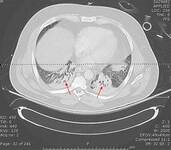

CT scan of a patient with a large, dense left lower lobe infiltrate

Consent obtained at University of Louisville, KY